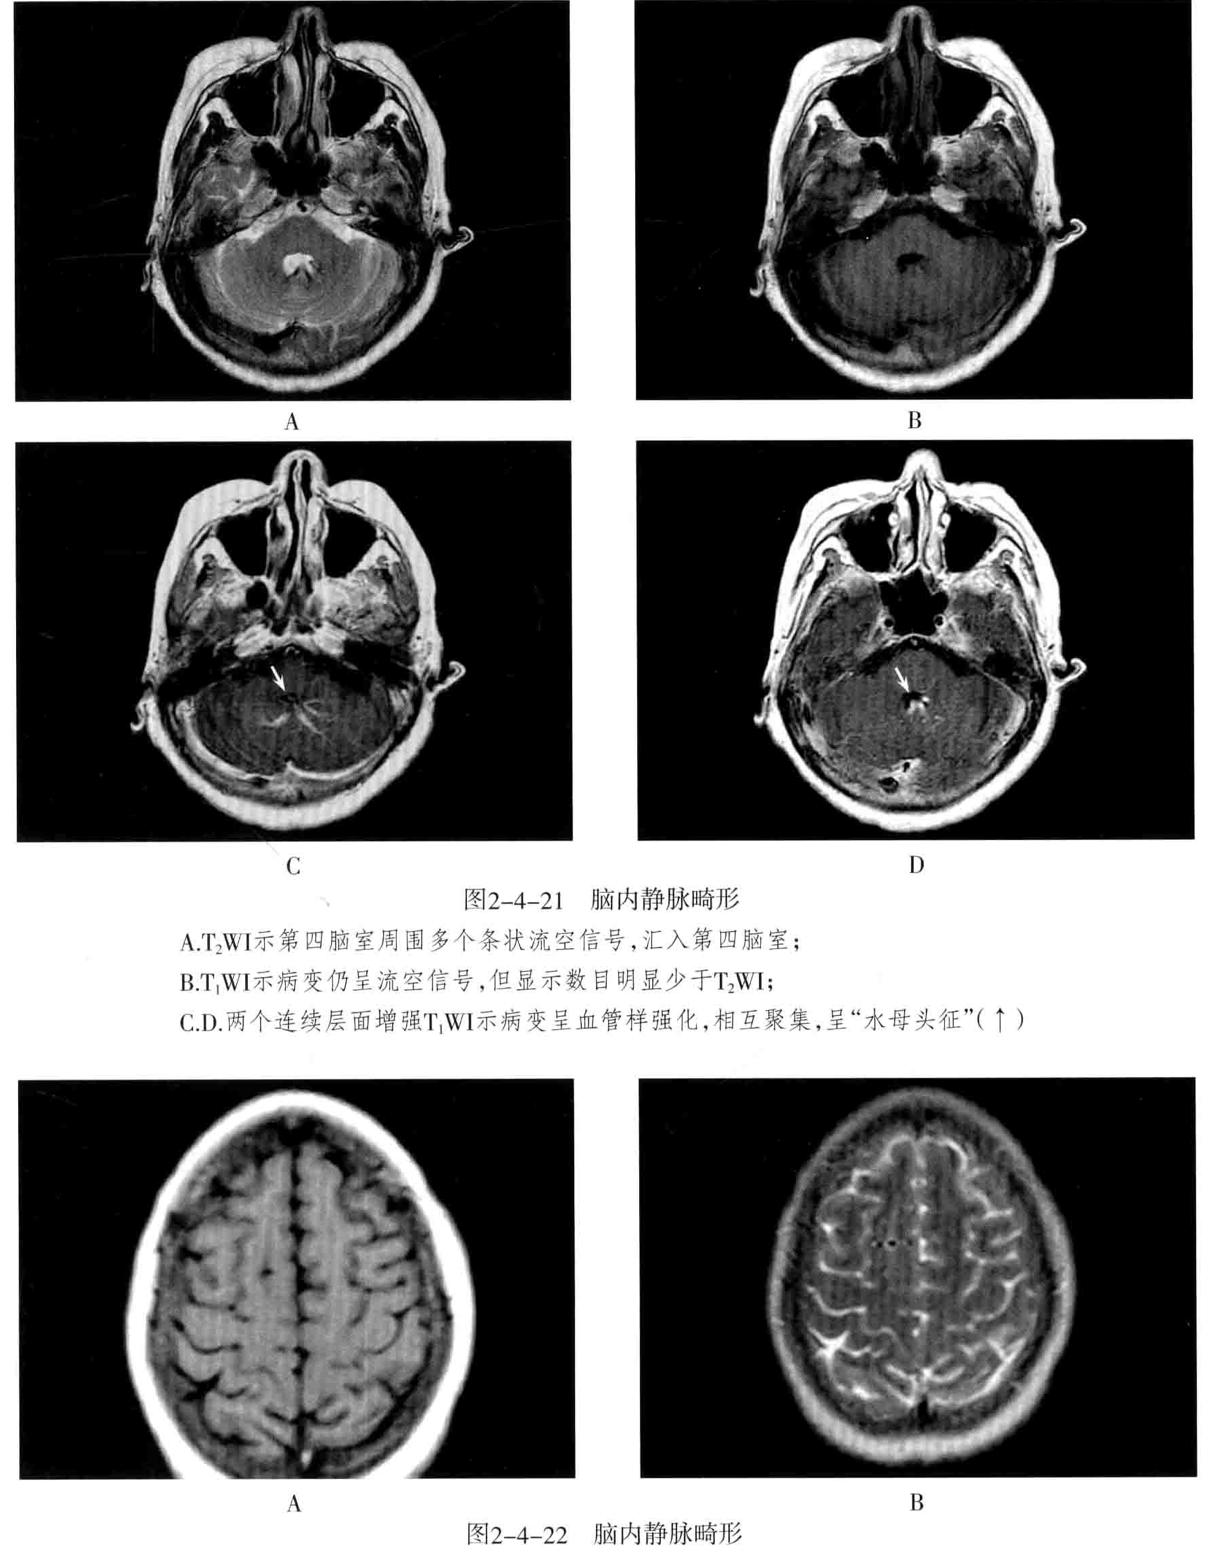

1. 脑静脉性血管瘤 极为少见。静脉性血管瘤是一种组织上完全由静脉成分构成的脑血管畸形,任何年龄均可见,病理特点为许多放射状排列的扩张髓静脉连接成一条或多条扩张的经皮质或室管膜下引流静脉,最后汇入静脉窦。常发生于 额叶及小脑,以第四脑室周围多见 ,常伴发其他血管畸形,最常见为海绵状血管瘤。

2. CT表现:平扫显示不清,周围无脑水肿,有时可见出血等改变,CTA典型表现为额叶或小脑许多细小髓静脉放射状汇入一条或几条引流静脉,最后汇入静脉窦,呈“水母头征”。

3. MRI表现:可因病灶大小及血流速度不同而在MRI上呈多种信号,T1WI、T2WI多呈流空信号,少数由于血流缓慢也可呈略高信号,FLAIR呈低信号。增强后髓静脉及引流静脉明显强化,典型者呈“水母头征”,引流静脉可走向脑表面而引流至静脉窦,或走向脑室引流至室管膜静脉。MRV可显示引流静脉及其引流情况,但不显示髓静脉,SWI序列对本病显示很敏感。病灶周围无脑水肿表现,有时可见出血。